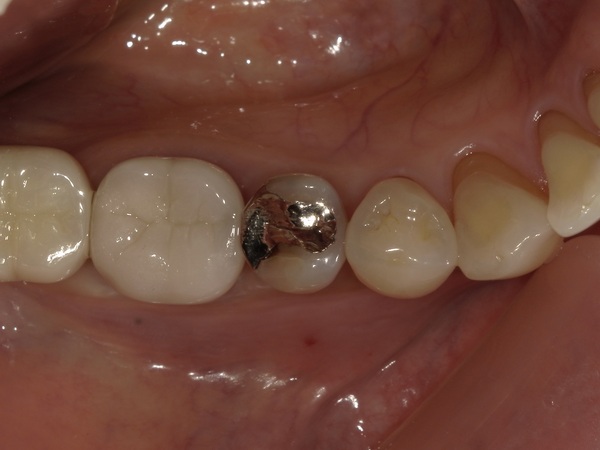

患者様は60代の女性で、主訴は「右下の銀歯の違和感」でした。

こちらが初診時の銀歯(メタルインレー)の写真になります。

右下5番目の歯には、数年前に保険診療により別の歯科医院で装着された銀歯が入っていました。よく見ると、銀歯と歯の境目が黒くなっているのが分かります。